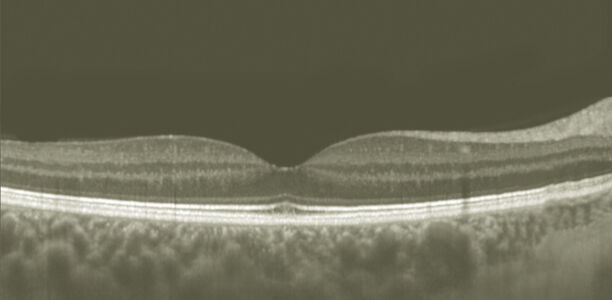

Zahlreiche metabolische Erkrankungen gehen mit ophthalmologischen Veränderungen einher, welche jedoch über lange Zeit symptomlos bleiben und im Regelfall erst erkannt werden, wenn das Sehvermögen bereits eingeschränkt ist. In diesem Zusammenhang nimmt die Retina als ein vaskularisiertes neuronales Gewebe und Teil des Zentralnervensystems eine besondere Rolle ein. Ihre Zugänglichkeit ermöglicht es, vaskuläre und neurodegenerative Veränderungen mit Hilfe der optischen Kohärenztomographie (OCT) als einem nicht invasiven Verfahren darzustellen.

Neurodegenerative Veränderungen der Retina bei pädiatrischen Patienten mit Typ-1-Diabetes

© Augenheilkunde Universitätsmedizin Rostock